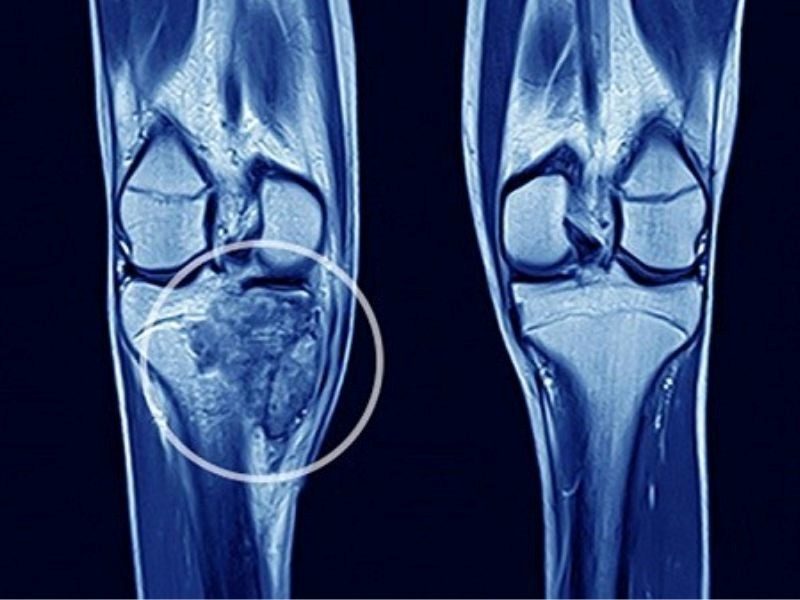

Ung thư xương có chữa được không là vấn đề được nhiều người quan tâm, đặc biệt đối với những bệnh nhân bị mắc căn bệnh này. Bài viết dưới đây Fucoidan Care sẽ giúp bạn hiểu chi tiết về vấn đề này:

Khả năng điều trị ung thư xương phụ thuộc vào nhiều yếu tố, bao gồm loại ung thư, mức độ lan rộng của bệnh và tình trạng sức khỏe của bệnh nhân. Quy trình điều trị ung thư xương khá phức tạp, với các phương pháp điều trị chính thường bao gồm phẫu thuật, hóa trị và xạ trị. Mỗi phương pháp có ưu và nhược điểm riêng, yêu cầu một kế hoạch điều trị cá nhân hóa để tối ưu hóa hiệu quả và giảm thiểu rủi ro cho từng bệnh nhân.